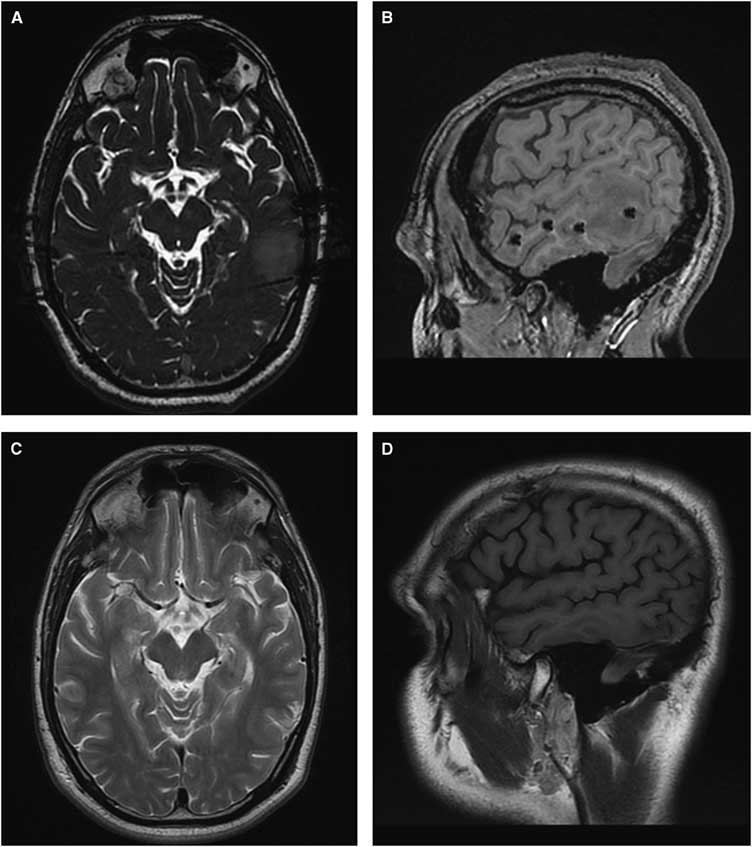

Frontiers Changes Over Time Of Diffusion Mri In The White Matter Of Aging Brain A Good Predictor Of Verbal Recall Frontiers In Aging Neuroscience

www.frontiersin.org